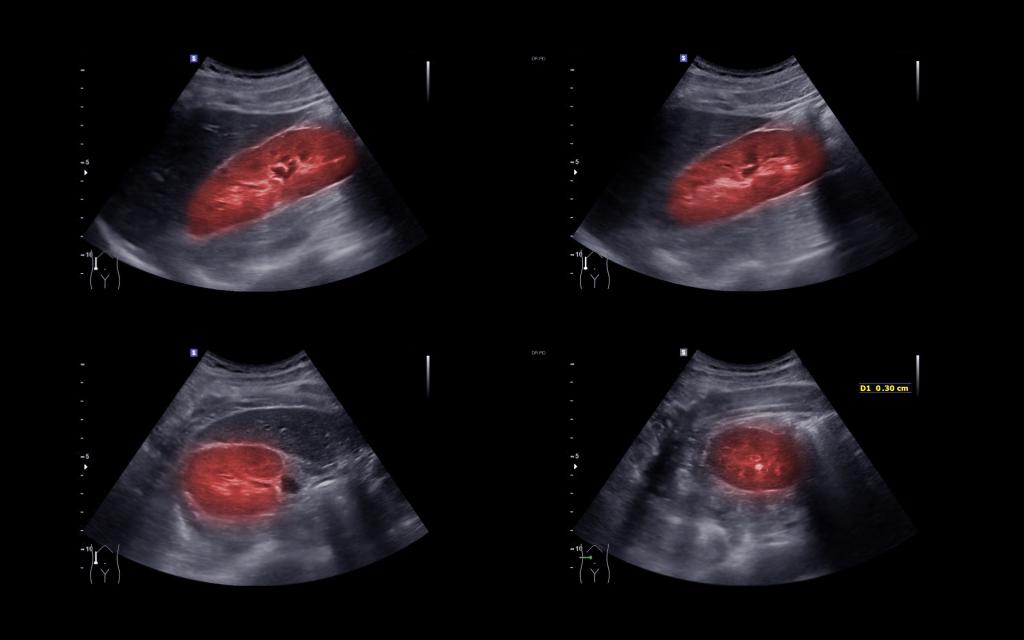

【护理科普知识宣传活动】肾囊肿健康小科普